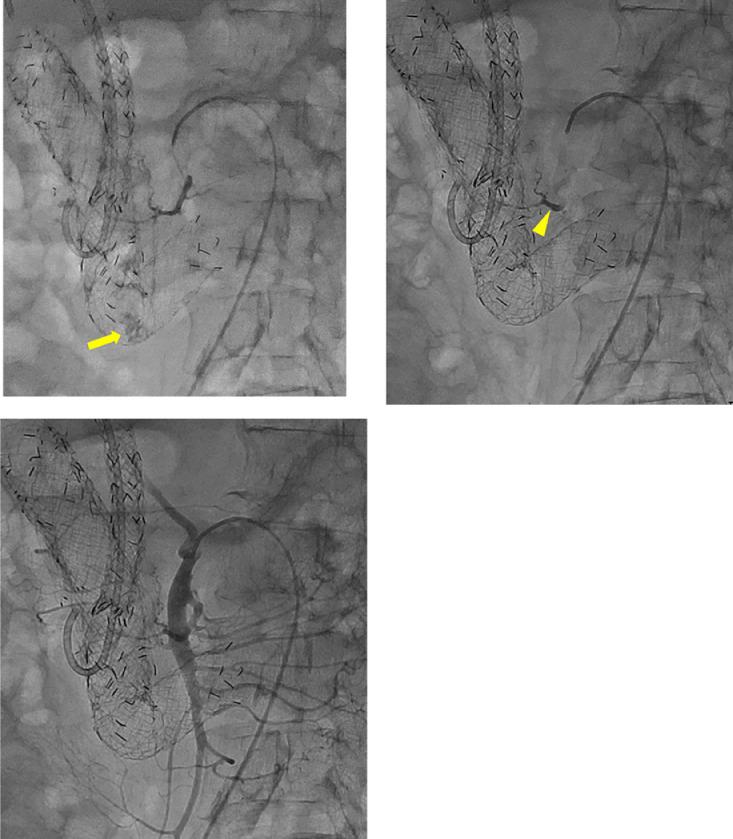

The patient was a man in his 60s who previously underwent placement of covered stents in the duodenum for a duodenal stricture caused by pancreatic cancer invasion. He experienced multiple episodes of hematemesis and hematochezia during hospitalization. Emergency upper and lower gastrointestinal endoscopies were performed but were unable to reveal the bleeding source. Based on these findings, we suspected small intestinal bleeding and emergency angiography was performed for the purpose of hemostasis. Computed tomography during arteriography was performed from the superior mesenteric artery and revealed extravasation outside the covered stents in the descending portion of the duodenum. Angiography of the inferior pancreaticoduodenal artery revealed extravasation in the descending portion of the duodenum, and the inferior pancreaticoduodenal artery was embolized with -butyl cyanoacrylate. There were no postoperative symptoms indicative of intestinal ischemia or pancreatitis, and there was no rebleeding after embolization. In patients with bleeding outside the duodenal-covered stents, it can be difficult to identify the bleeding source by upper gastrointestinal endoscopy. In this case, selective computed tomography during arteriography and angiography revealed bleeding outside the duodenal-covered stents that was successfully treated by arterial embolization with -butyl cyanoacrylate.

该患者为一名60多岁的男性,此前因胰腺癌侵犯导致十二指肠狭窄,接受了十二指肠覆膜支架置入术。他在住院期间经历了多次呕血和便血。进行了急诊上、下消化道内镜检查,但未能发现出血源。基于这些发现,我们怀疑是小肠出血,并为了止血进行了急诊血管造影。动脉造影期间从肠系膜上动脉进行了计算机断层扫描,显示十二指肠降部覆膜支架外有造影剂外渗。胰十二指肠下动脉造影显示十二指肠降部有造影剂外渗,并用氰基丙烯酸正丁酯栓塞了胰十二指肠下动脉。术后没有出现提示肠缺血或胰腺炎的症状,栓塞后也没有再出血。对于十二指肠覆膜支架外出血的患者,通过上消化道内镜检查可能难以确定出血源。在本病例中,动脉造影期间的选择性计算机断层扫描和血管造影显示十二指肠覆膜支架外出血,通过用氰基丙烯酸正丁酯进行动脉栓塞成功治疗。